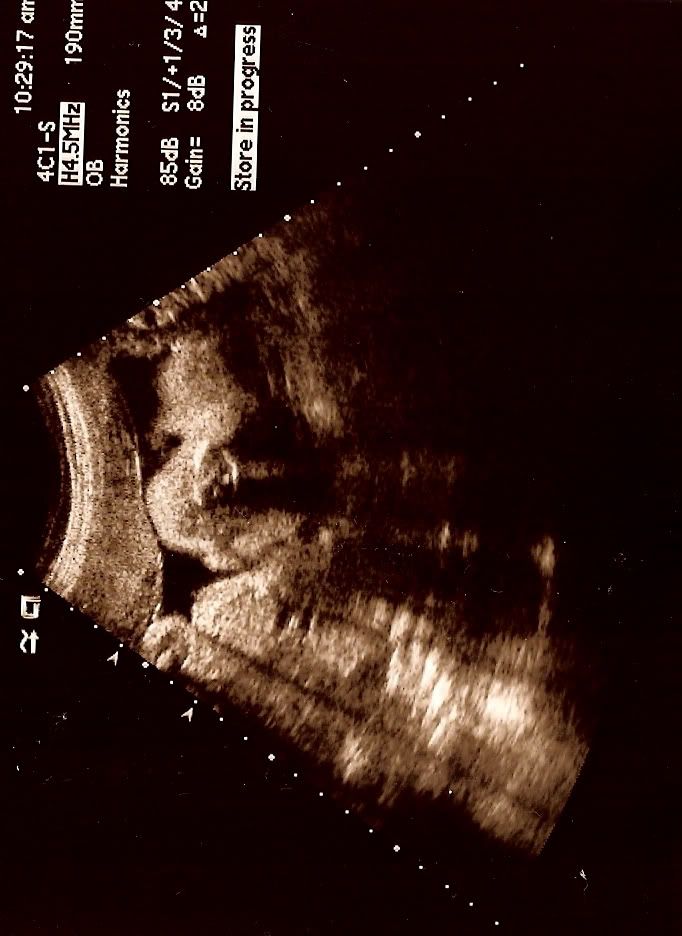

超声波又来了!

昨天又去照超声波了,早上我还特地和了两杯果汁,让宝宝"活动活动", 好让我们可以看得清楚点。

可是哦。。。宝宝让我们失望了。我觉得是因为他长大了,我的肚子/他活动的空间边小了,虽然感觉到肚子里的他在踢,在动,可是从银幕上却没有看到什么明显的动作。

可是好过没有啦,只要看到就好了,最重要的是,医生说他一切看起来正常。看到他的小手小脚,后来还看到他部分的脸!为什么说"部分"呢?因为小宝宝不懂是害羞还是"号链",把自己的脸遮起来,所以我们只看到"部分"的脸咯。

不过哦,他的脸颊看起来有点肉肉的,象是"叉烧包脸"哦。。我跟老公看了都在笑,因为我们喜欢有婴儿肥的宝宝,尤其是包包脸,以后一定常被我们捏脸颊的,哈哈!真的很感动,每照一次超声波就感动一次。。

最近这两次的超声波医生都给我们DVD,还算不错啦。

宝宝30周又5天,医生说他的体重有3磅8安士。 还有大概9个星期,我们就要跟宝宝见面了。很期待哟!!!

宝宝超声波的照片,我把它打直了,希望你们看得到他的"包包脸", 哈哈!